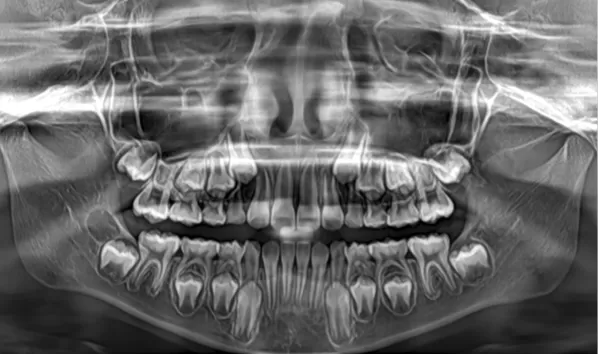

Rayons X avant le traitement

[Radiographie panoramique/Céphalogramme latéral]